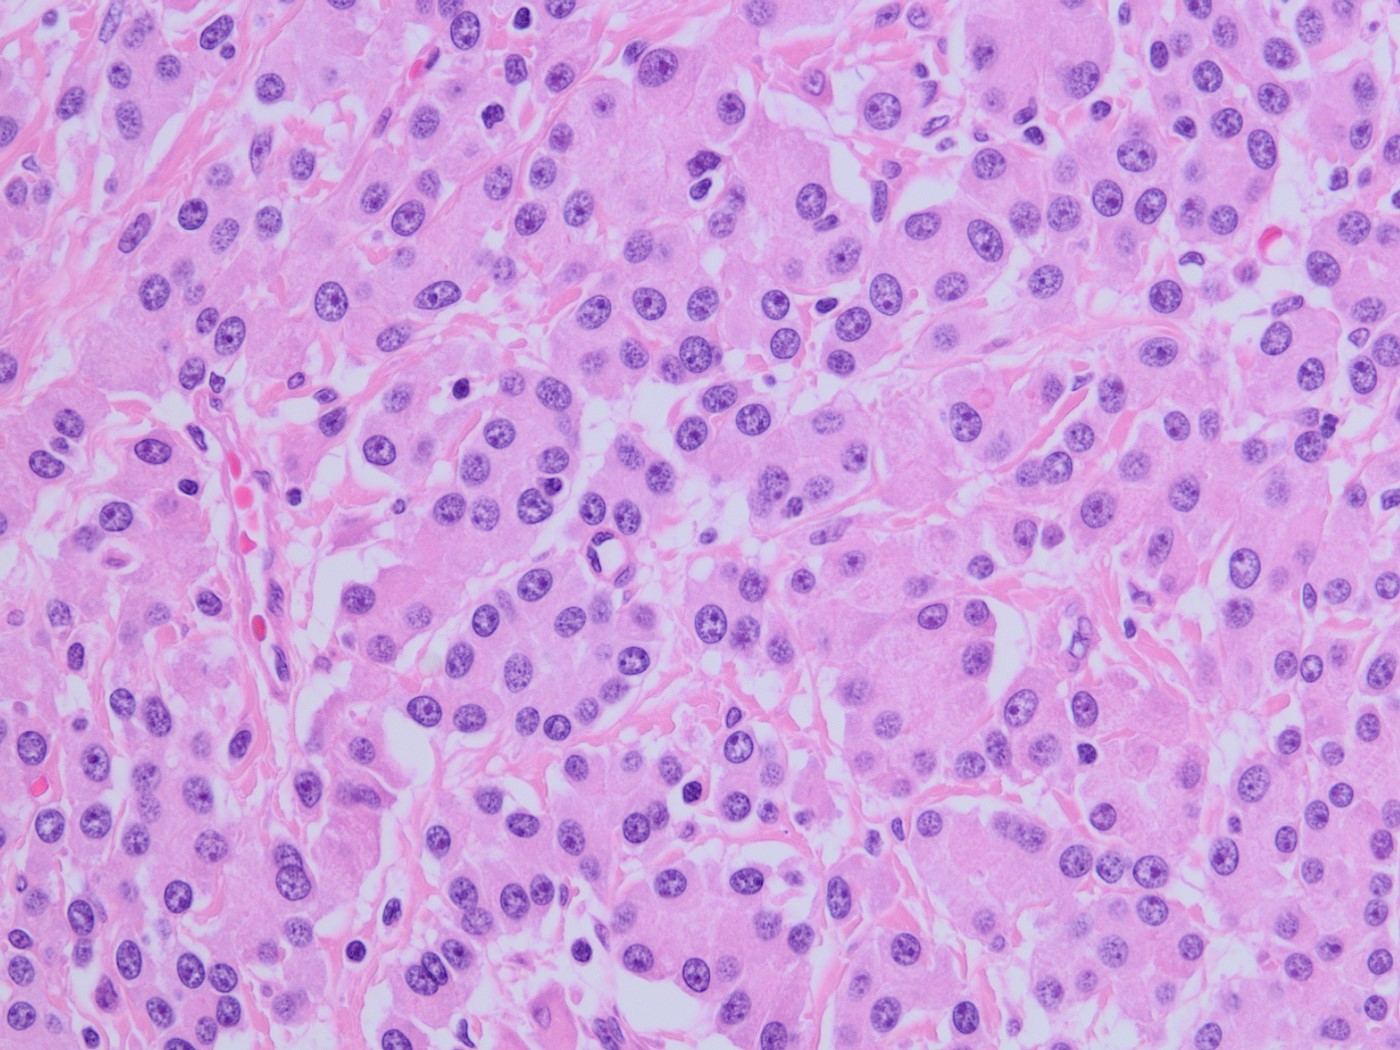

A 75-year-old woman with suspected pancreatic NET undergoes a Whipple. The morphology of the tumor is seen in Fig A-D. A synaptophysin is performed (Fig E). What additional IHC profile can be expected in this tumor?

The tumor is solid and cellular with the individual cells displaying abundant granular cytoplasm and round monotonous nuclei with prominent nucleoli, configured in a vague acinar formation. These features are consistent with an acinar cell carcinoma, therefore positive staining for trypsin and BCL10 are expected (figures).

The main differential diagnosis in this case is a well differentiated neuroendocrine tumor. However, a stain for synaptophysin stain is negative, with an islet serving as an internal control. This finding rules out a neuroendocrine tumor, therefore chromogranin would also likely be negative. Acinar cell carcinoma can sometimes have weak staining for neuroendocrine markers, however the KI67 index should be high in acinar cell carcinoma. Pancreatoblastoma is also an important differential diagnosis for acinar cell carcinoma. The background of pancreatoblastoma is often that of an acinar pattern with corresponding trypsin positivity. However, pancreatoblastoma will contain squamoid nests that show nuclear staining for beta-catenin. Solid pseudopapillary neoplasm (SPN) should also be considered as a differential, as it is a solid and cellular neoplasm with bland cytology. However, acinar cell carcinoma lacks the distinctive small capillaries and pseudo papillae formation seen in SPN. SPN will also have characteristic nuclear beta catenin staining.